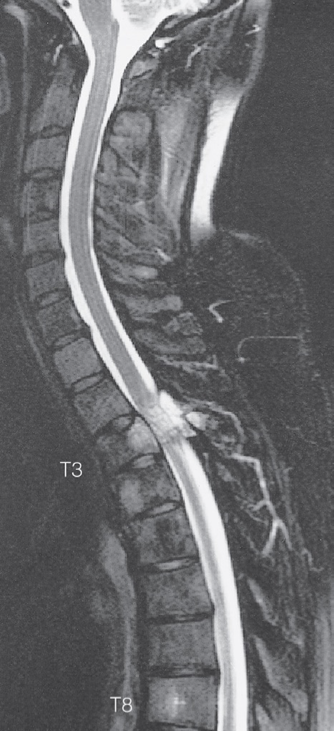

Spinal cord compression. - T2-weighted MRI scan

showing metastases from a breast carcinoma in the body and pedicle of T3 causing compression of the spinal cord.